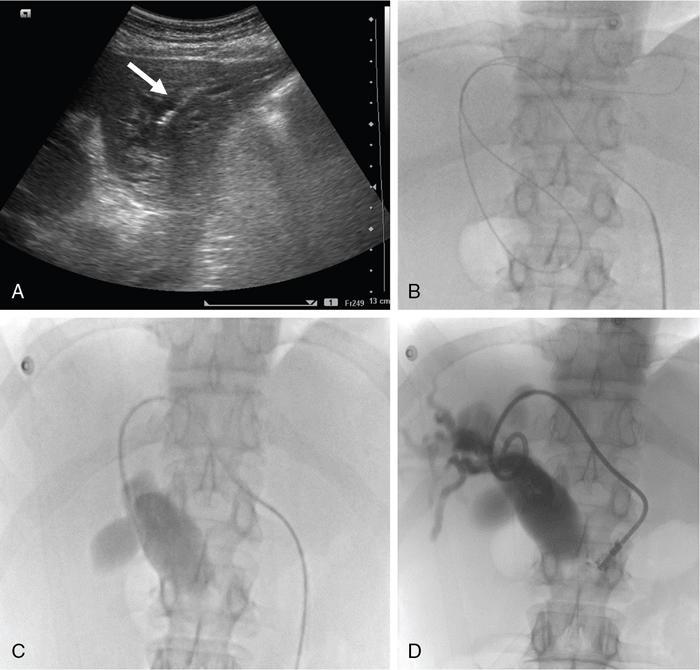

The relief of obstructive jaundice following the placement of a percutaneous transhepatic catheter was first described by Dr William Molnar and Dr Alfred Stockum in 1974. This technique involves aseptic percutaneous puncture of a peripheral biliary radicle, followed by fluoroscopy-guided wire and catheter manipulation and insertion a drainage catheter (pigtail or ring biliary catheter) or stent for drainage. PTBD is performed as a therapeutic and as a palliative procedure. The indications for PTBD can be divided into malignant and benign causes (Table 9.24.1). The aims of PTBD in these indications are shown in Table 9.24.2. For malignant aetiologies, PTBD is useful in preoperative and palliative settings, and for benign aetiologies it may be a bridging procedure before a definitive surgery or therapeutic. Hyperbilirubinemia limits the selection of chemotherapeutic agents. Chemotherapeutic agents such as anthracyclines (doxorubicin), topoisomerase inhibitors (irinotecan) and the taxanes require intact mechanisms of bilirubin excretion to prevent toxicity. Bilirubin level less than 2–3 mg/dL is usually considered safe for most of these agents. In addition, preoperative biliary drainage helps in the reduction of renal toxicity caused by bilirubin and thus reduces surgical morbidity. Altered enterohepatic circulation due to biliary obstruction leads to symptoms such as anorexia and altered food taste and these symptoms are relieved with biliary drainage. Pruritus is another such symptom which hampers quality of life. Drainage of even one liver segment causes significant relief in pruritus. Various intrabiliary procedures such as brush biopsy, brachytherapy and RFA (explained later in the chapter) can be done through the same route. Benign biliary strictures (BBSs) usually require percutaneous approach as endoscopy is either difficult, such as in postoperative bilioenteric anastomotic strictures or has failed, as in tight distal strictures precluding bile duct or ampullary cannulation. Biliary diversion through PTBD is important in cases of posttraumatic bile leak to prevent peritonitis and sepsis. Uncommonly, in cases where the benign bile duct strictures extend to the hepatic hilum and intrahepatic parts of distal segmental ducts, it may be difficult for the surgeon to locate the duct intraoperatively. In such situations, percutaneous placement of a catheter preoperatively facilitates duct identification at surgery. There are no absolute contraindications. Relative contraindications are coagulation disorders, allergy to iodinated contrast agents and ascites. In cases with abnormal coagulation profile requiring emergency biliary drainage (patients in cholangitis with risk of septicaemia), fresh frozen plasma should be given before and during the procedure. In elective cases, vitamin K injection may be given for 3 days and procedure should be done after normalization of coagulation parameters. In rare emergent scenarios where coagulation profile of the patient is not known, drainage can be done immediately. However fresh frozen plasma should be kept ready. Large-volume ascites causes technical difficulty and predisposes to peritonitis and bleeding. Thus, ascites must be drained prior to PTBD. In cases of allergy to a particular iodinated contrast agent, a different category of contrast agent may be used. Before performing the procedure, the following aspects must be evaluated. Reviewing baseline imaging is the most vital step required to perform a successful biliary intervention. All patients requiring a percutaneous biliary intervention should have had a multiphase contrast-enhanced cross-sectional imaging, either computed tomography (CT) scan or magnetic resonance imaging (MRI) before the procedure. Both modalities are equally accurate in assessing the cause and level of obstruction and outlining the extent of the disease. CT and MRI also provide an assessment of the volume of hepatic parenchyma. MRCP provides information about the extent of biliary dilatation, level of obstruction and presence of any variations in biliary anatomy. Bile duct obstructions can be high or low, above or below the level of cystic duct insertion, and identifying this is important. Distal obstructions are usually managed endoscopically, and percutaneous interventions are required when endoscopic drainage is unsuccessful, is contraindicated or when it is not technically possible. For high obstructions, percutaneous approach is easier and more targeted and thus preferred. A multidisciplinary team is involved in the final management decision which is tailored to each patient. Ultrasonography (USG) plays a considerable role during PTBD. It assists in screening the patient prior to any percutaneous radiological procedure, where it helps in the assessment of the extent of dilatation of the bile ducts, status of the primary and secondary confluences (patent or blocked), volume of the liver segments or lobes being drained, and presence or absence of ascites. Knowledge of these helps to decide the approach used, lobe to be drained and the hardware needed. A review of patient’s blood parameters is also required. The most relevant parameters are prothrombin time (PT) and international normalized ratio (INR). The PT values should not be more than 4 seconds above the control value and INR be below 1.5. The platelet count should be more than 50,000/μL. Renal function tests (blood urea nitrogen and serum creatinine) also need to be reviewed before the procedure, although it does not usually alter the management. The patient should be admitted in the hospital prior to the procedure. In elective cases, at least 3 hours of fasting for solids is required. An informed consent is required with mention of the catheter care required postprocedure. Intravenous access should be secured. Antihypertensive medications should not be skipped; oral hypoglycaemic agents and insulin should be avoided in view of fasting. Biliary drainage has been classified as clean-contaminated or contaminated according to the Society of Interventional Radiology and thus requires antibiotic prophylaxis. A dose of intravenous antibiotics (preferably third-generation cephalosporins and metronidazole to cover anaerobic bacteria) should be given 1 hour prior to the procedure, as transient bacteremia commonly occurs during PTBD. If more than 2 hours lapse from the initial dose, the dose may be repeated. Patients should be hydrated with 0.5–1 L normal saline prior to the procedure. Fluids can be chosen based on requirement. The procedure is usually performed under local anaesthesia (2% lignocaine) and light conscious sedation (midazolam or fentanyl may be used). Screening USG is repeated to replan the approach and to rule out ascites. All the hardware required should be kept ready (Figs. 9.24.1 and 9.24.2). The procedure is performed with the patient in supine position. The skin area, depending on whether the right or left or both ductal system needs drainage, is cleaned and draped. Local anaesthesia (2% lignocaine) is injected along the planned tract, up to the liver capsule. Then, a small nick is given on the skin using a surgical blade. The sectoral bile duct (usually segment 3 for left- and segment 6 for right-sided PTBD) is punctured peripherally using an 18G Chiba needle, under USG guidance (Fig. 9.24.3). Central duct punctures are more prone to vascular injuries and may also provide inadequate drainage of hepatic lobes.